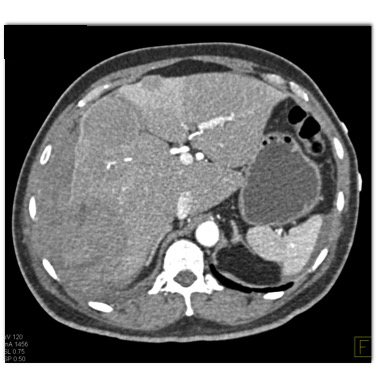

In this patient with RUQ pain the least likely diagnosis is?

hepatic adenoma

hepatoma

metastatic neuroendocrine tumor

hemangioma